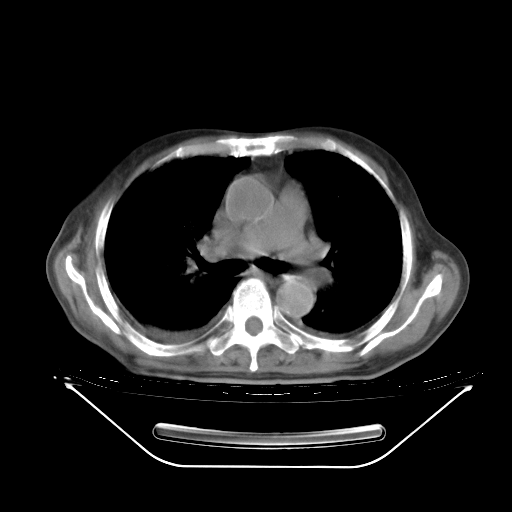

今天复查肺部CT,发现双肺广泛磨玻璃样改变。所以我把3月19日和5月9日相隔50天的肺部CT上传。请大家会诊。

2009年3月19日肺部CT片。

5月9日肺部CT(在4月27日齐鲁医院肺部CT描述部分肺组织磨玻璃样改变,12天后肺组织广泛磨玻璃样改变)

大致读了系列胸部CT:纵隔窗无明显异常,肺窗:从4、27至今:主要是双肺中下野外带可见毛玻璃样改变,目前处于急性肺泡炎阶段,至于原因考虑1、结替组织或胶原血管性疾病所致?2、恶性疾病如恶组在肺部所致的表现或细支气管肺泡癌?3、药物或其它原因如肺蛋白沉着症所致肺泡炎目前不太可能?总之,明天就去请我院的呼吸科、感染科、血液科和临免专家会诊哈。